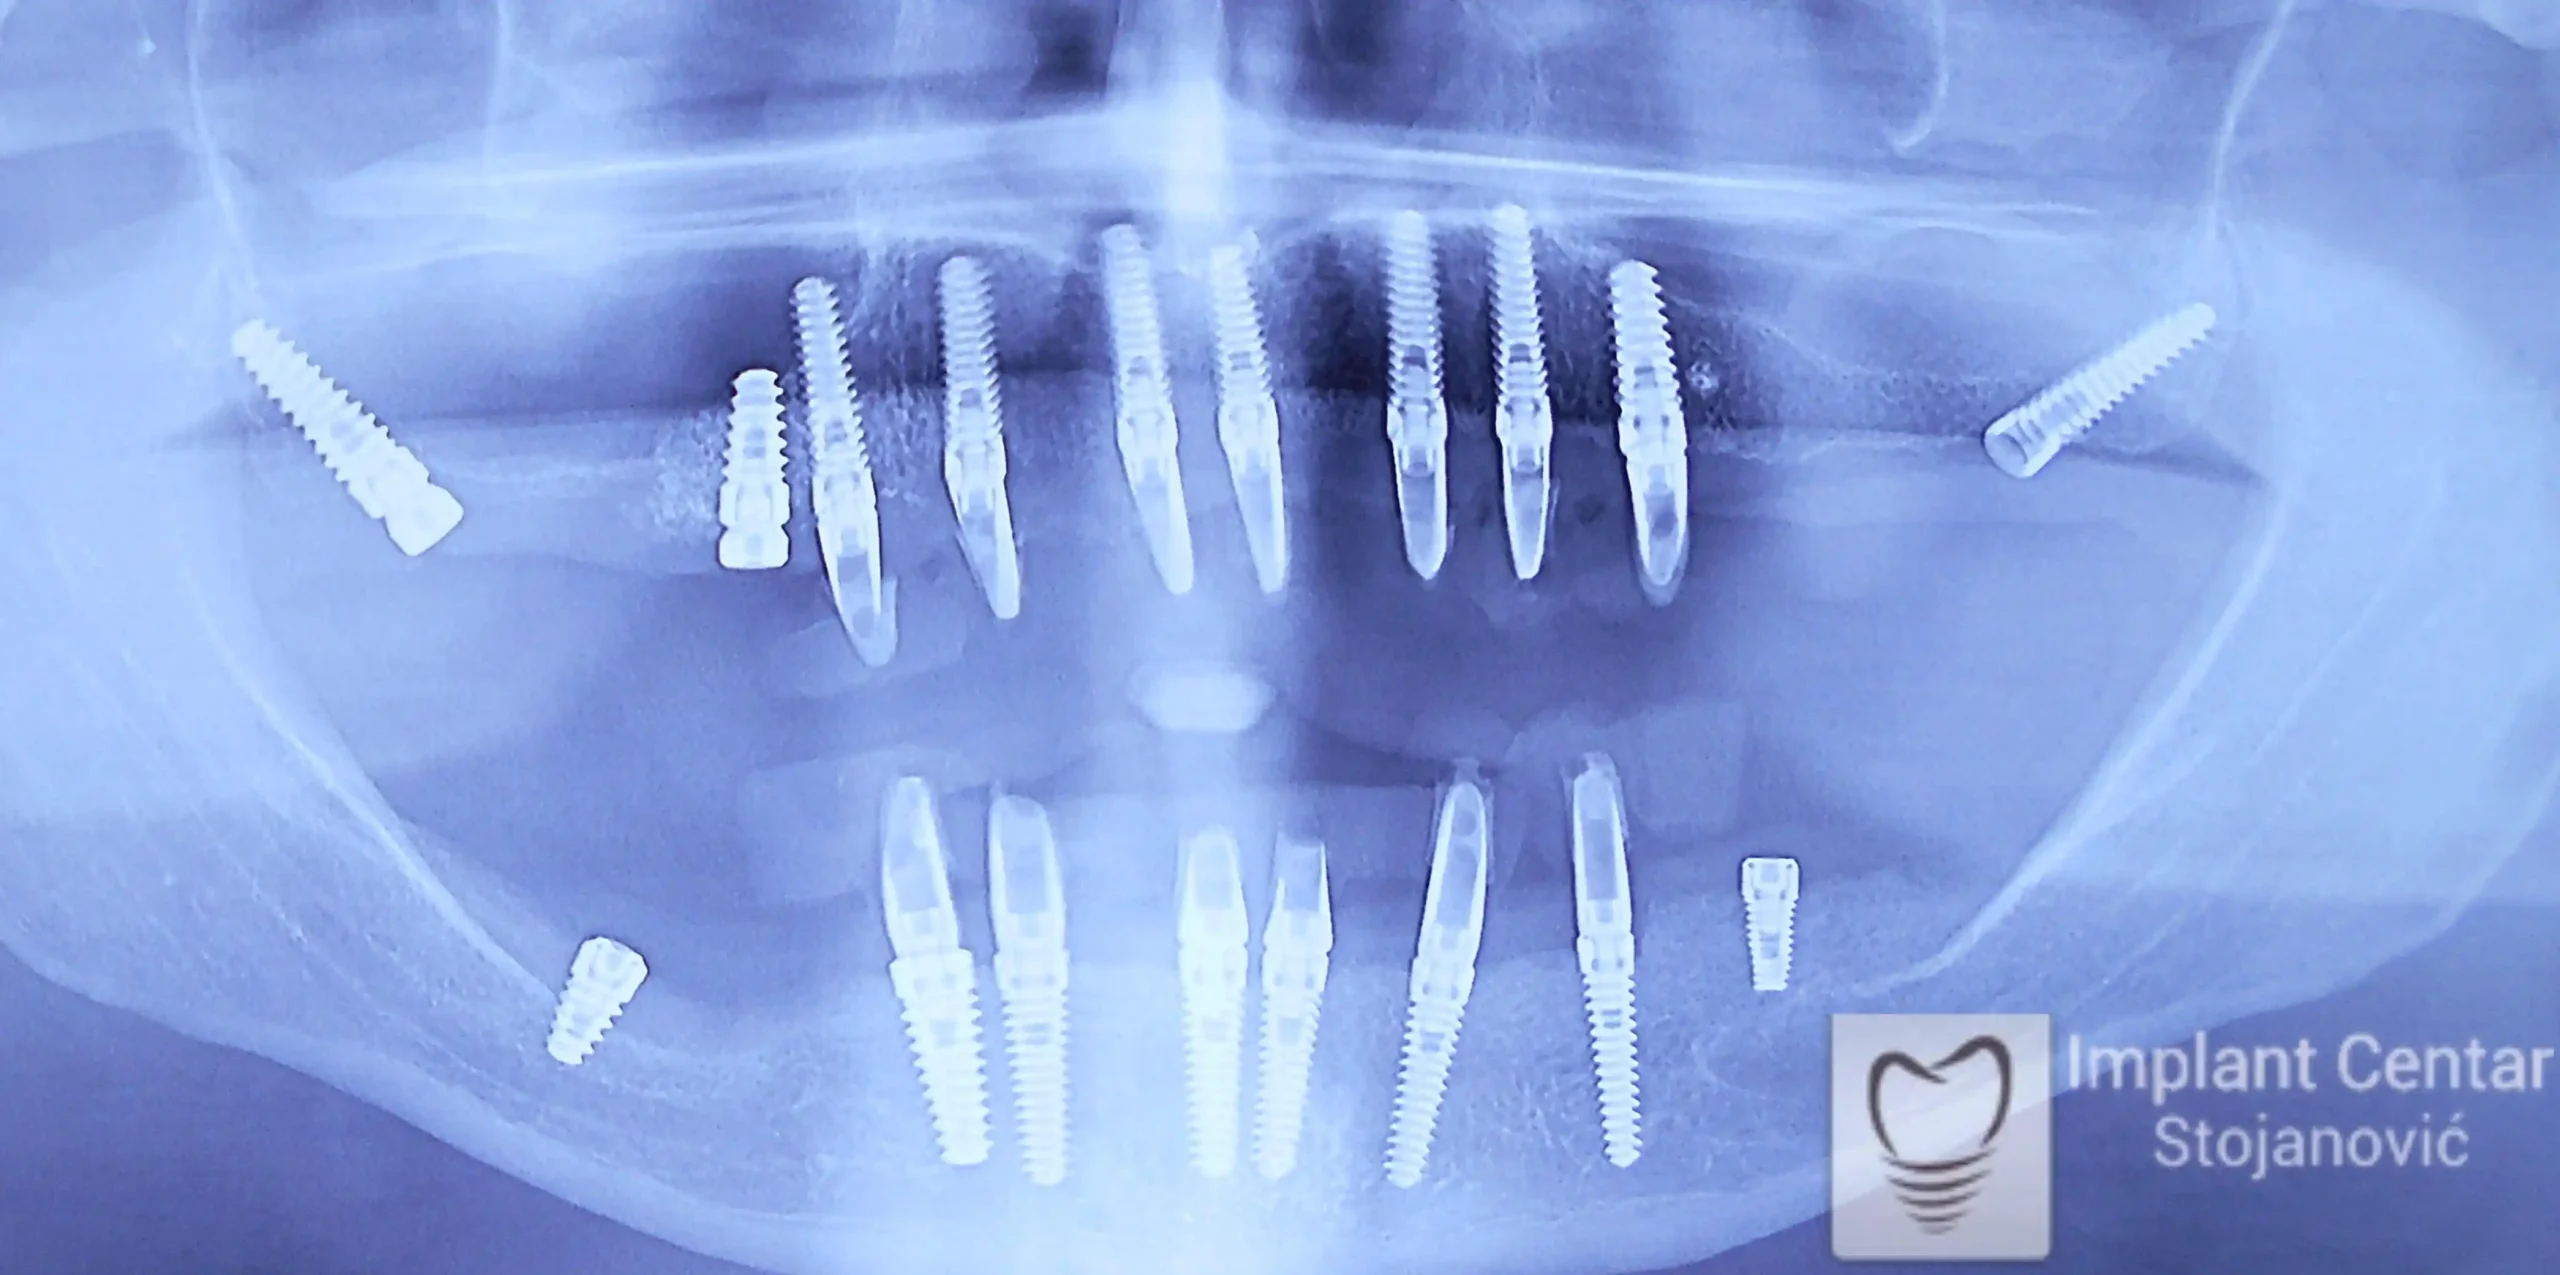

Nakon vađenja zuba, ugrađeni su implantati. Na slici 3 prikazan je ortopan snimak sa ugrđenim implantatima. Tokom perioda osteointegracije, pacijent je bio zbrinut fiksnim privremenim krunicama na implantatima, koje su izrađene samo dva dana nakon hirurške intervencije.

Na slikama 5. i 6. prikazan je izgled definitivnih cirkonijum-keramičkih mostova na implantatima.